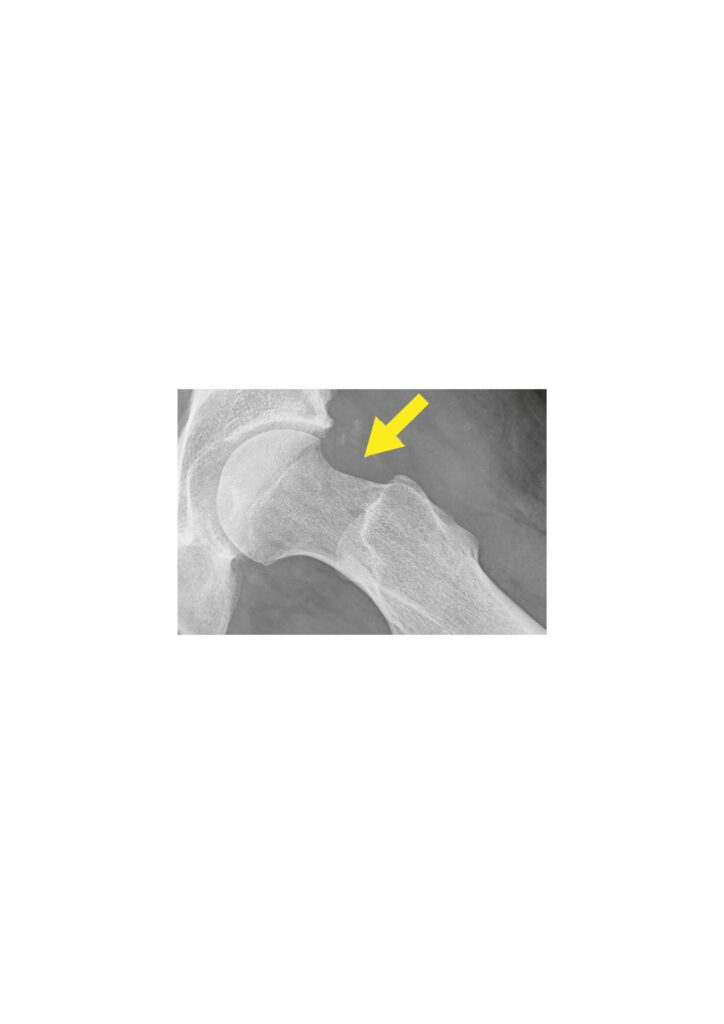

Hüftarthroskopie (Gelenkspiegelung):

- Minimalinvasive Technik mit kleinen Hautschnitten

- Behandlung von Labrumrissen

- Korrektur des femoroazetabulären Impingements (FAI)

Minimal-invasive, offene Operationen:

- Umformung bei Wulstbildung am Kopf-Hals-Übergang bei CAM-Impingement

- Umformung bei Randwülsten der Pfanne bei Pincer-Impignement